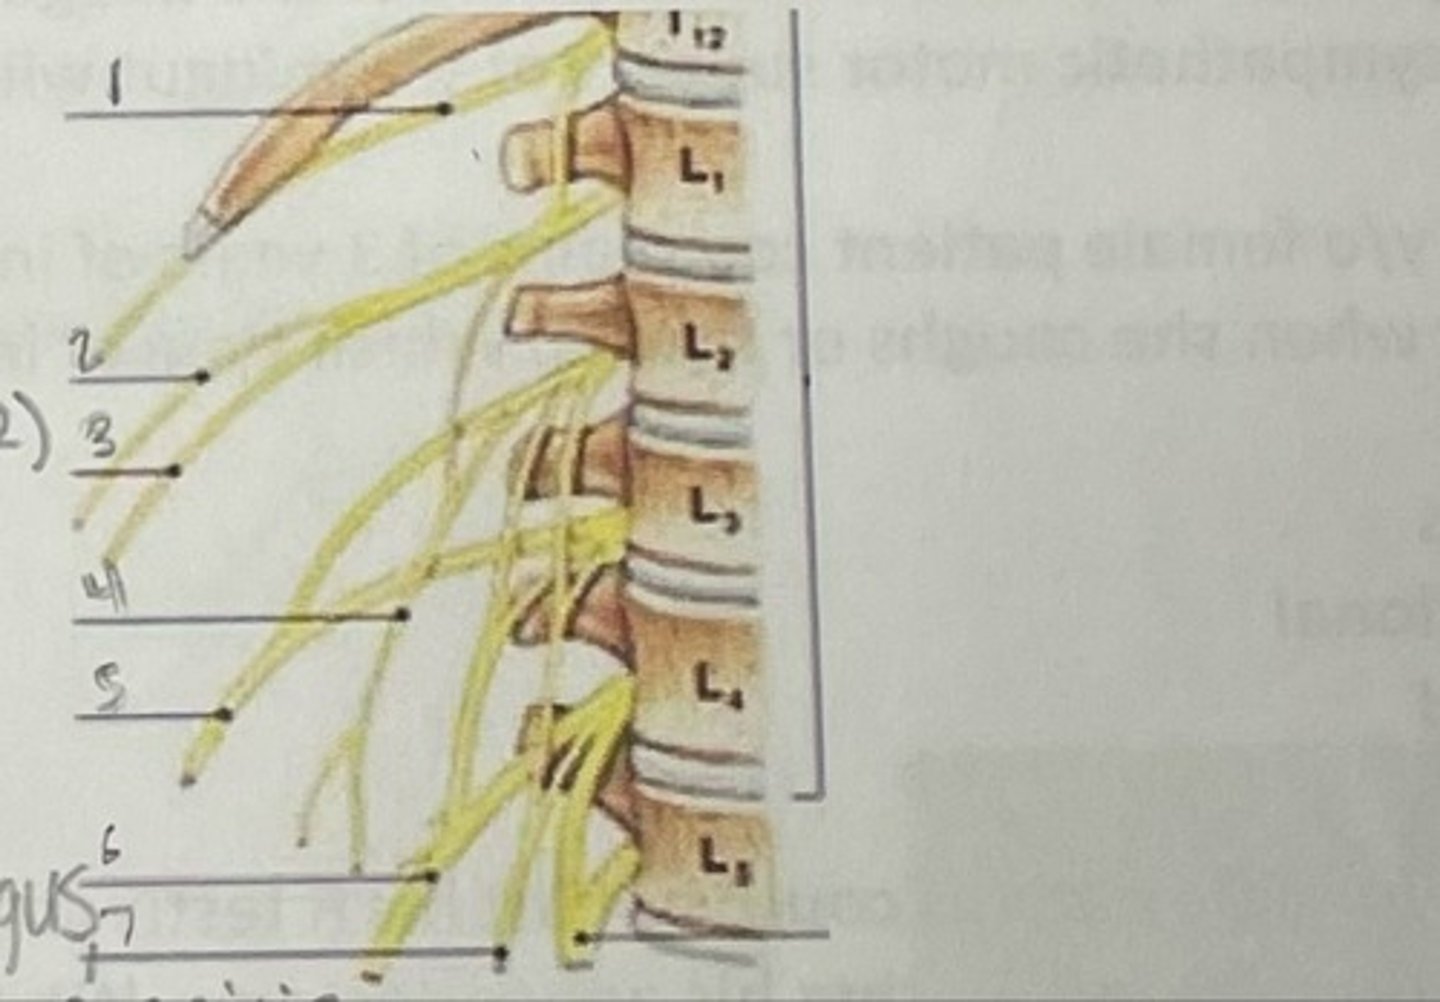

Subcostal nerve (T12)

What is 1

Illiohypogastric nerve (T12/L1)

What is 2

Illioinguinal nerve (L1)

What is 3

Genitofemoral nerve (L1-L2) ; on top of psoas

What is 4

lateral femoral cutaneous nerve (L2-L3)

What is 5

Femoral Nerve (L2-L4)

What is 6

Obturator nerve (L2-L4)

What is 7